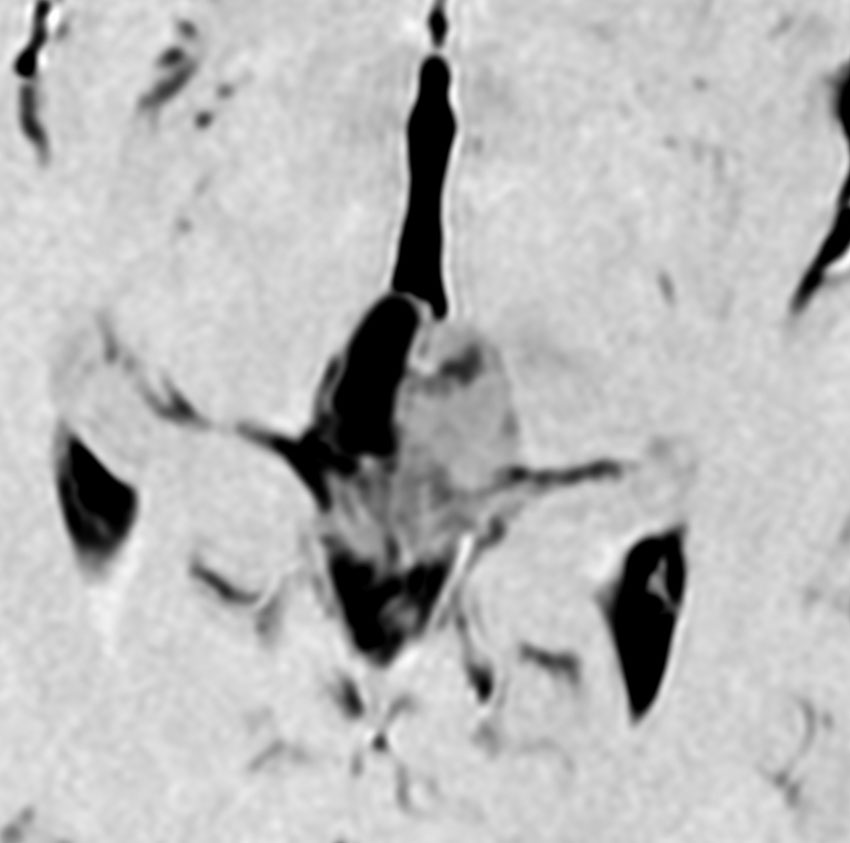

これも偶然発見された無症状の女性の小さい松果体細胞腫ですが,ほとんど実質性でのう胞がありません。右はCISSという画像です。中脳の視蓋は圧迫されて変形していますが,中脳水道がまだ閉塞していないのがよくわかります。